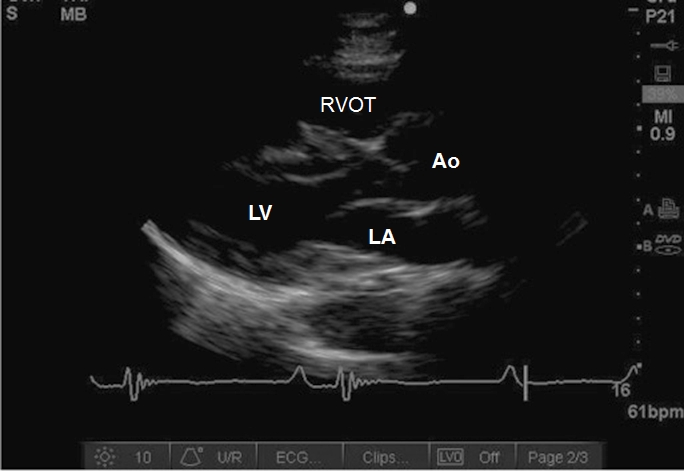

Case 7-1. Parasternal Long-axis View

Video 7-1A. This video demonstrates the importance of performing the initial view with a depth setting that allows visualization of structures posterior to the heart. In this case, there is a pleural effusion with atelectatic lung floating within it. This would be missed if the depth setting were set initially to place the heart in central screen position.

Video 7-1B. Depth setting adjusted to place the heart in central screen position. There is severe reduction of left ventricular (LV) function with a segmental wall abnormality involving the anterior septum. The septum is thin and the LV cavity is dilated suggesting chronic LV dysfunction related to ischemic injury. Diastolic excursion of the anterior mitral valve (MV) is reduced consistent with reduced LV function. Chamber size and wall thickness would require formal measurement with M-mode or direct caliper measurement.

Video 7-1C1. Color Doppler interrogation of the mitral valve with what is likely moderate mitral regurgitation (MR). The examiner is required to enlarge the color grid to cover the entire left atrium in order to give an more accurate qualitative estimate of the severity of the MR. The cause of the MR is not evident by morphological pattern, while the segmental wall abnormality suggests the possibility of ischemic origin.